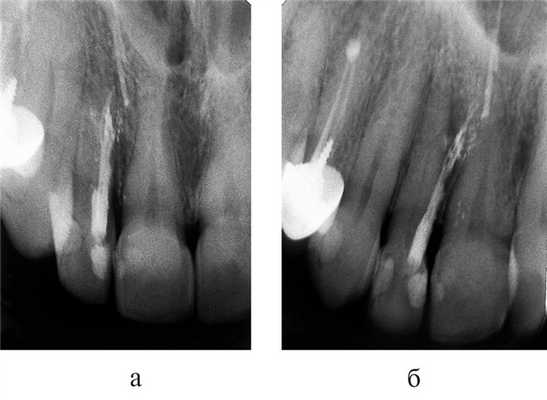

Часто резорбцию выявляют случайно при рентгенологическом исследовании по другому поводу [23] . На рентгенограмме внутренняя и внешняя резорбция будут выглядеть по-разному.

Рентгенологические признаки наружной и внутренней резорбции корня зуба

Воспалительная и заместительная резорбция рентгенологически очень похожи. Но при заместительной резорбции из-за образования кости на снимке не видно просветления в области периодонтальной щели.

Рентгеновское обследование зубов (дентальные рентгенограммы) — самым простой, быстрый и доступный метод диагностики. Но в сложных случаях, когда не удаётся поставить диагноз, лучше использовать компьютерную томографию (КТ). Этот метод более информативный [22] [23] [26] .